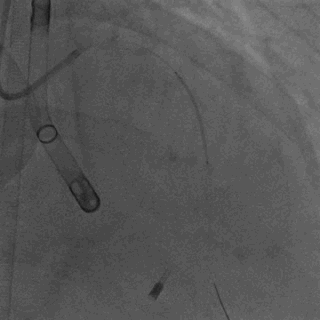

患者经历了右髋关节置换术后,左心搏动泵得以从左侧股动脉入路顺利置入。浙江大学医学院附属第二医院心内科蒋峻主任首先用CTO导丝尝试开通回旋支闭塞病变,但由于患者长期患有糖尿病和肾功能不全,病变坚硬,导丝通过困难。考虑到患者正处于心衰急性期且肾功能不全,蒋峻教授迅速调整了治疗策略,优先处理前降支病变,预扩张后快速植入支架。

术中患者无不适症状,左心搏动泵工作状态稳定,术中监测LVEF可达41.0%, 血流动力学稳定,PCI术后即刻撤除搏动泵。患者于术后8天顺利出院,出院前复查LVEF恢复至42.1%。本次浙大二院王建安院士团队成功完成国产经皮左心搏动泵支持下高风险PCI手术,进一步显示出晟视科技新一代介入式左心搏动泵在临床应用中的有效性和安全性。